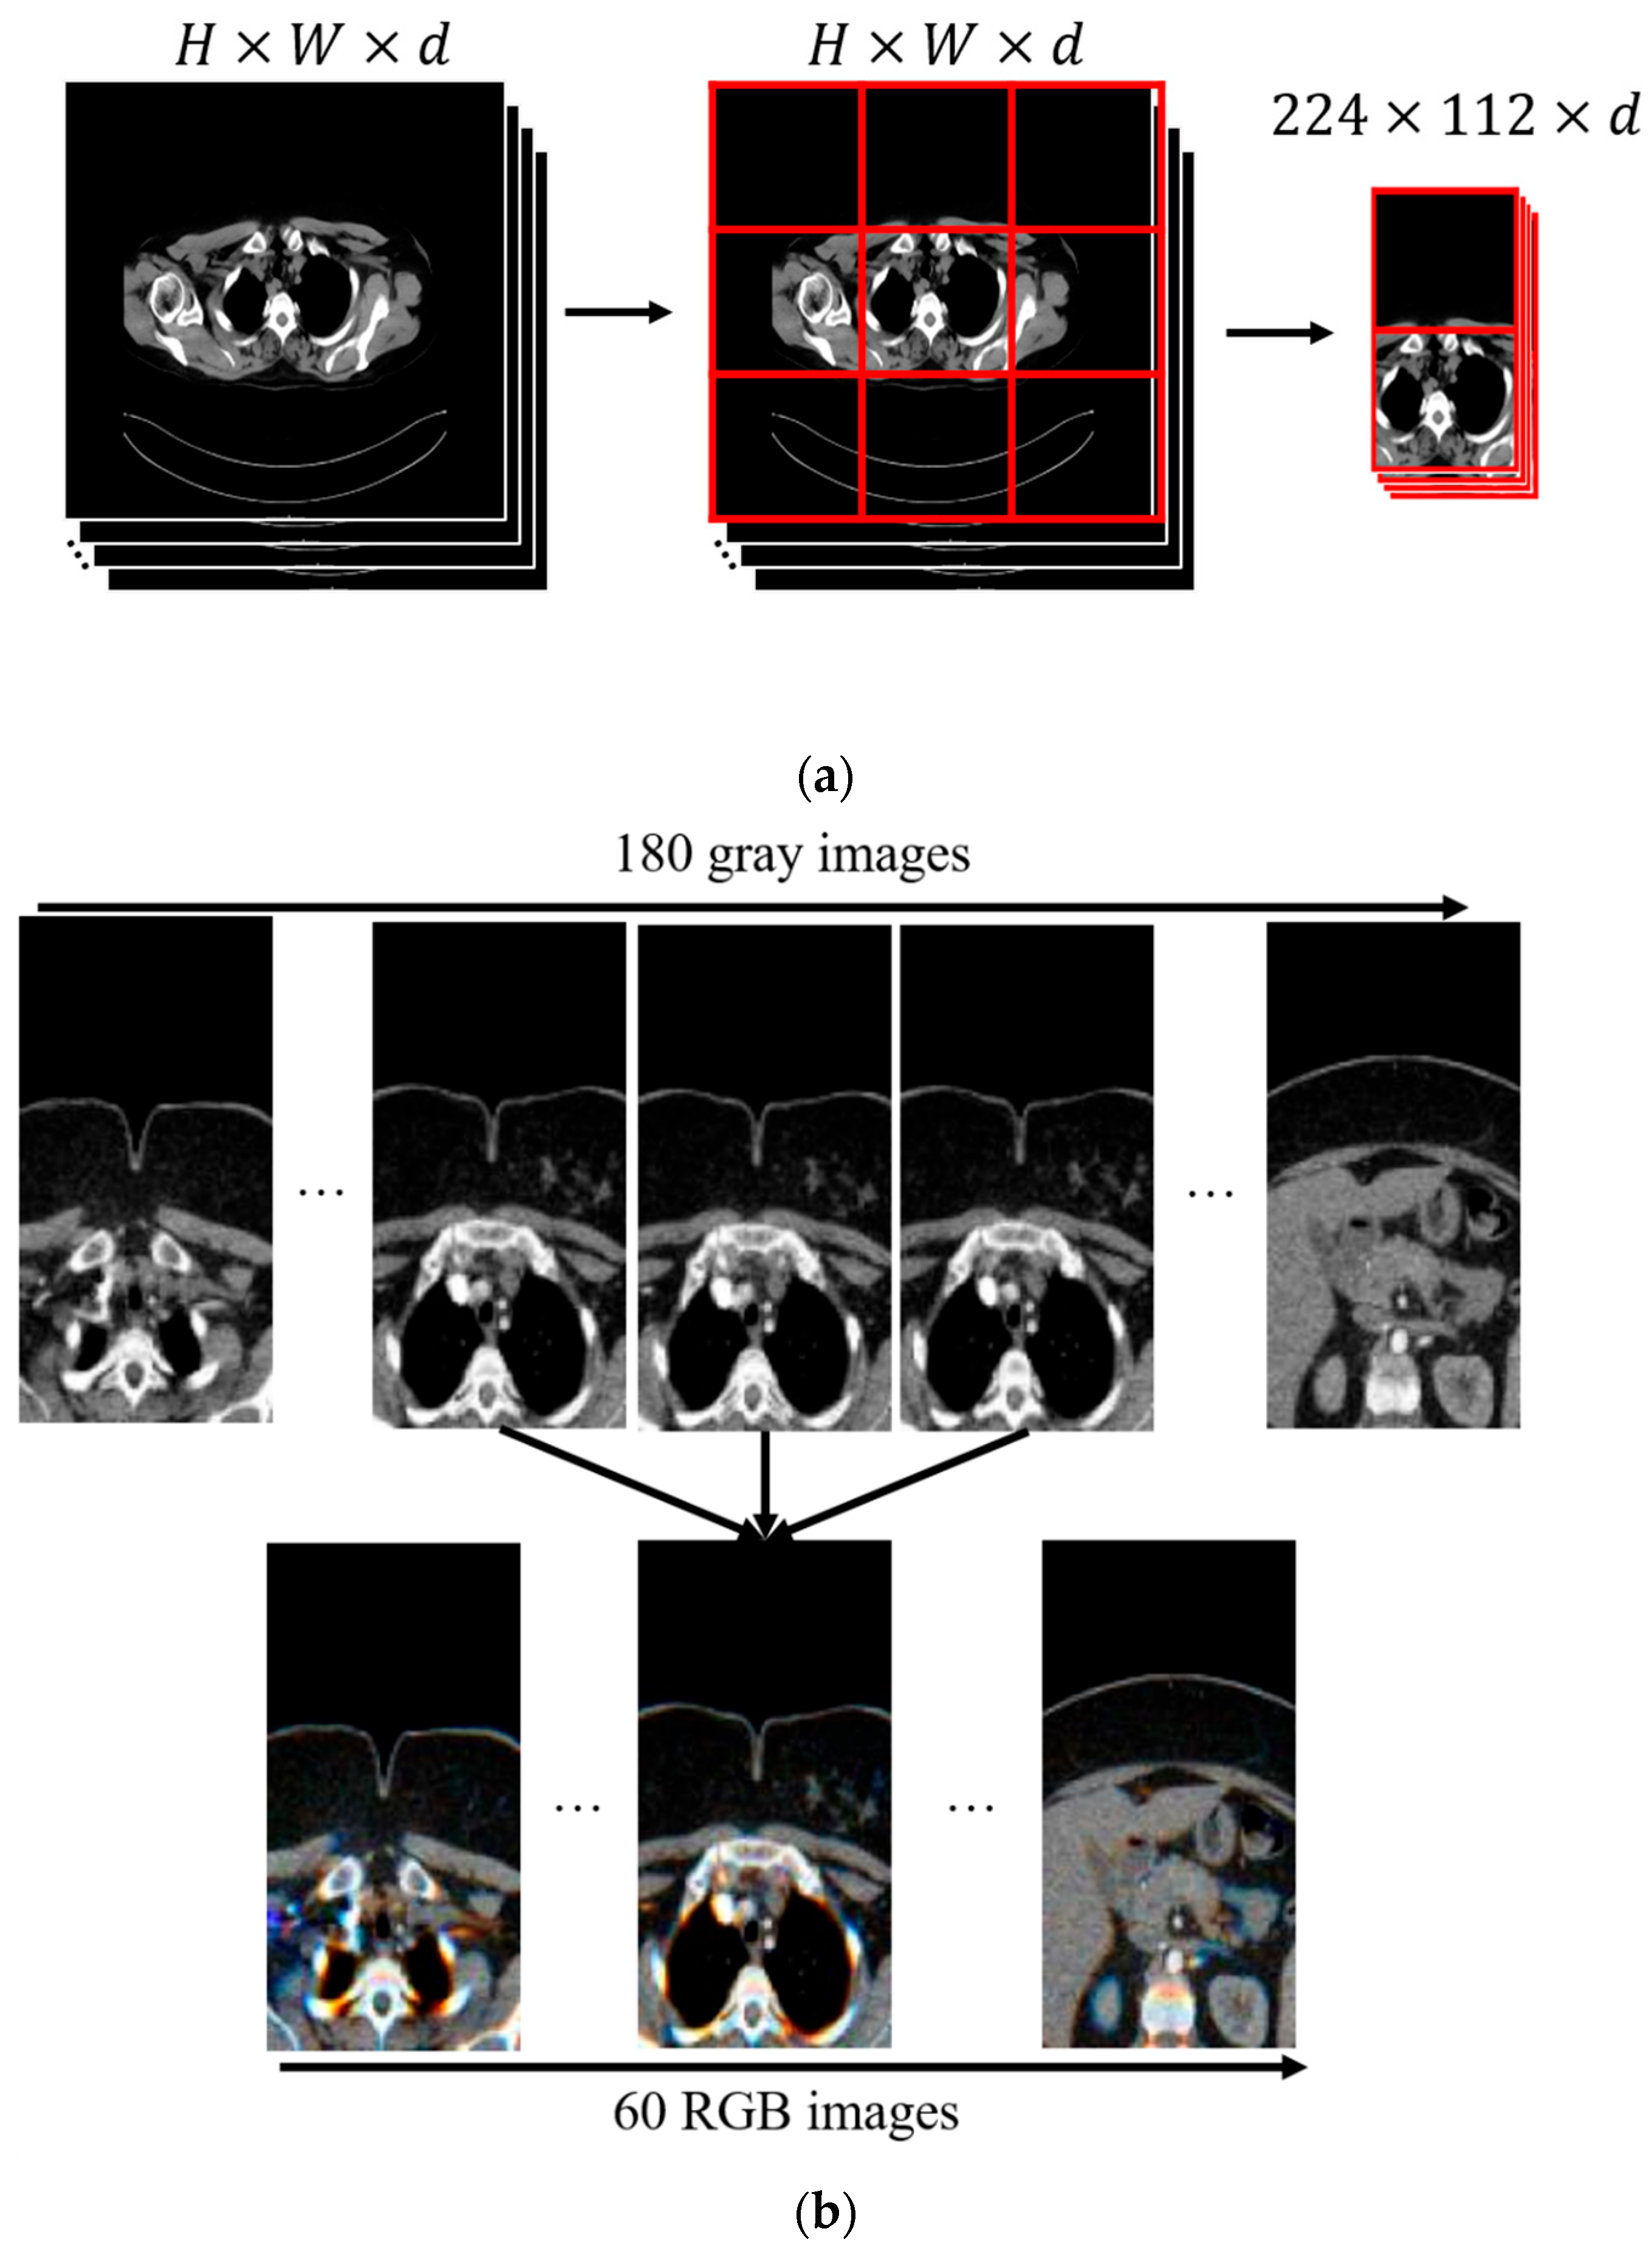

The CT image dataset used in this study was obtained from the Department of Thoracic Surgery, Turgut Ozal Medical Center, Inonu University. A total of 198 patients were included in the study, consisting of 120 healthy individuals and 78 thymoma patients. Among the thymoma patients, 46 were diagnosed with benign thymoma and 32 with malignant thymoma. Before preprocessing, the dataset contained 31,685 CT slices from healthy individuals, 576 slices from malignant thymoma cases, and 602 slices from benign thymoma cases. A preprocessing pipeline, including normalization, slice selection, and resizing, was applied to ensure consistent image quality. After this stage, the number of usable slices was reduced to 10,383 for healthy individuals, 132 for malignant thymoma, and 306 for benign thymoma. All CT images were anonymized prior to analysis. Preprocessing was performed at the slice level to remove low-quality frames and standardize the images for use in the deep learning models. A patient-based 5-fold cross-validation strategy was used to ensure reliable and independent evaluation of model performance. In this approach, patient identity—not individual slices—was used to separate training and testing sets, preventing any slices from the same patient from appearing in both subsets within a fold. In each fold, approximately 80% of the patients (around 158 individuals) were assigned to the training set, while the remaining 20% (around 40 individuals) formed the testing set. The folds were constructed to maintain the overall patient distribution as closely as possible, including 120 healthy patients, 46 benign thymoma patients, and 32 malignant thymoma patients. This ensured that each fold represented the general structure of the full dataset. Example CT images from the dataset are presented in Figure 5.

Figure 5. Example CT images from the dataset.